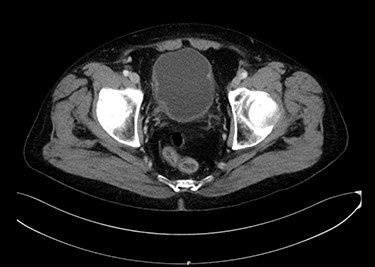

Seventy-year-old gentleman presented with an attack of gross hematuria and computed tomography scan showing irregularly thickened bladder wall. Endoscopic resection confirmed T1 MPBC. Induction course of BCG was provided. Cystoscopy showed small mass recurrence and pathology was muscle-invasive MPBC. Radical cystoprostatectomy sparing the urethra was done. Pathology was T2 MPBC with negative surgical margins and negative for lymph nodes invasion. He developed bleeding per urethra 6 months later and urethrectomy was done showing micropapillary cancer involving the urethra. Figure 2 shows an axial image of the bladder tumour.